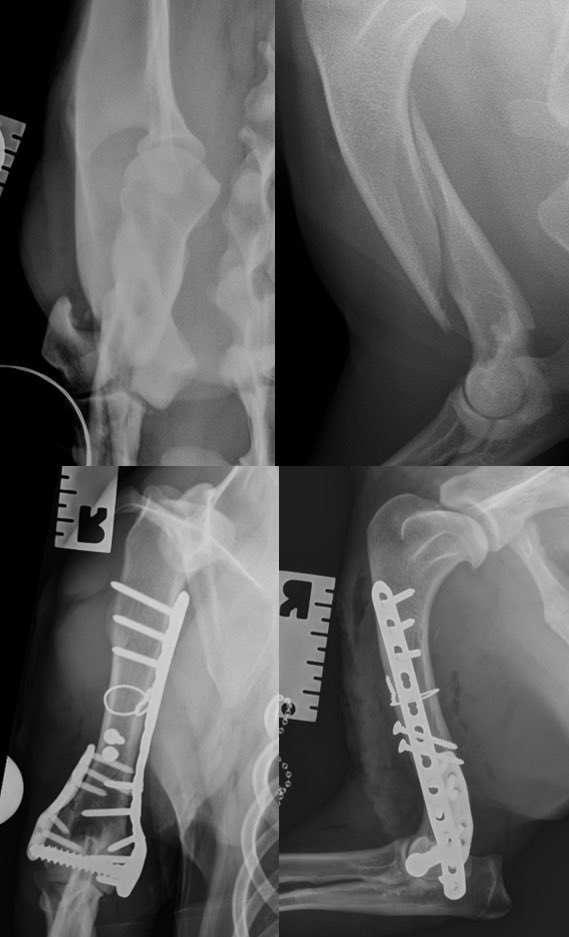

Meet Mac and his unusual, spiral dicondylar fracture. Kept me and the fantastic ⁦@CGVetSpecialist⁩ team busy today. Thank heavens for the ⁦Fusion Implants⁩ LEAP to save a bit of time@near the end.

Meet Mac and his unusual, spiral dicondylar fracture. Kept me and the fantastic ⁦@CGVetSpecialist⁩ team busy today. Thank heavens for the ⁦<a href="/FusionImplants/">Fusion Implants</a>⁩ LEAP to save a bit of time@near the end.

The Lateral Epicondylar Anatomical Plate from Fusion Implants is a great LEAP forwards. It makes repairing these fractures super-satisfying and provides a reliable locking plate construct for these dogs.

The Lateral Epicondylar Anatomical Plate from <a href="/FusionImplants/">Fusion Implants</a> is a great LEAP forwards. It makes repairing these fractures super-satisfying and provides a reliable locking plate construct for these dogs.